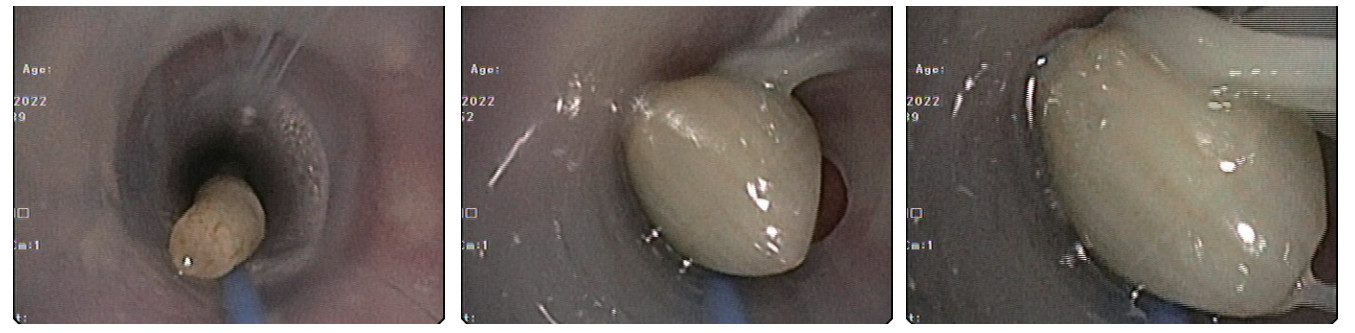

患者有明确高温暴露史,根据患者病史,查体及相关辅助检查,诊断“经典型热射病、Ⅰ型呼吸衰竭、支气管扩张伴感染、急性肾损伤”,继续予气管插管,呼吸机辅助呼吸,并每日监测气管插管气囊压力,迅速物理降温,抗感染,抗凝,补液扩容改善循环等对症治疗,经积极治疗后患者呼吸,循环等各项生命体征趋于稳定。患者白细胞明显高于正常值,且淋巴细胞占比明显增高,行骨髓穿刺活检后血液科专科会诊,诊断为“慢性淋巴细胞白血病,骨髓增殖性疾病”。患者住院2 d后开始出现阵发性呼吸困难,发作时伴大汗淋漓,夜间尤为明显,持续数分钟到数十分钟不等,症状发作时经皮血氧饱和度下降至90%,潮气量由约400 mL下降至约300 mL,两肺听诊可闻及少许哮鸣音,患者既往有慢性支气管炎病史,考虑支气管哮喘发作引起气道痉挛,应用甲基强的松龙针40 mg静脉注射,调整呼吸机参数,后患者呼吸急促逐渐缓解。入院第3天复查胸部CT(见图 2):“两肺感染性病变,右肺中叶、左肺上叶部分支扩伴感染,两侧胸腔少量积液伴邻近两肺下叶膨胀不全,气管及左侧支气管内条状高密度影”。根据胸部CT结果,气管及左侧支气管内高密度影考虑气道内痰液阻塞,加强翻身拍背,吸痰等对症治疗。入院第4天凌晨,患者再次出现呼吸急促,大汗淋漓,两肺听诊可闻及少许哮鸣音,经皮血氧饱和度下降至83%,潮气量明显下降至200 mL左右,血气分析提示:“PaO2:48 mmHg,PaCO2:30.5 mmHg,SatO2:83%,BE:-5 mmol/L,AB:18.5 mmol/L”。继续糖皮质激素应用缓解气道痉挛,鼓肺吸痰,上调呼吸机参数等综合治疗,0.5 h后患者氧合无明显改善,不排除气道梗阻可能,立即行床边纤维支气管镜检查,镜下见气管及左主支气管内有2条奶油色活动性虫体,给予夹出,夹出虫体后患者呼吸逐渐平稳,氧合明显改善(支气管镜下虫体图片详见图 3)。2条虫体为活虫,放置在生理盐水中可见活动,测量虫体长度约25 cm,虫体直径约5 mm(虫体全图详见图 4),经本院感染科及市疾控中心会诊后认定2条虫体为蛔虫成虫,故此,患者诊断“蛔虫病”明确,治疗上予阿苯达唑片400 mg/d鼻饲, 连续服用2日,驱虫治疗后5 d内大便中总共排出蛔虫成虫12条,驱虫治疗效果显著,病情好转。

| 图 3 纤维支气管镜下见蛔虫虫体 |

| 图 4 蛔虫虫体实物照片 |